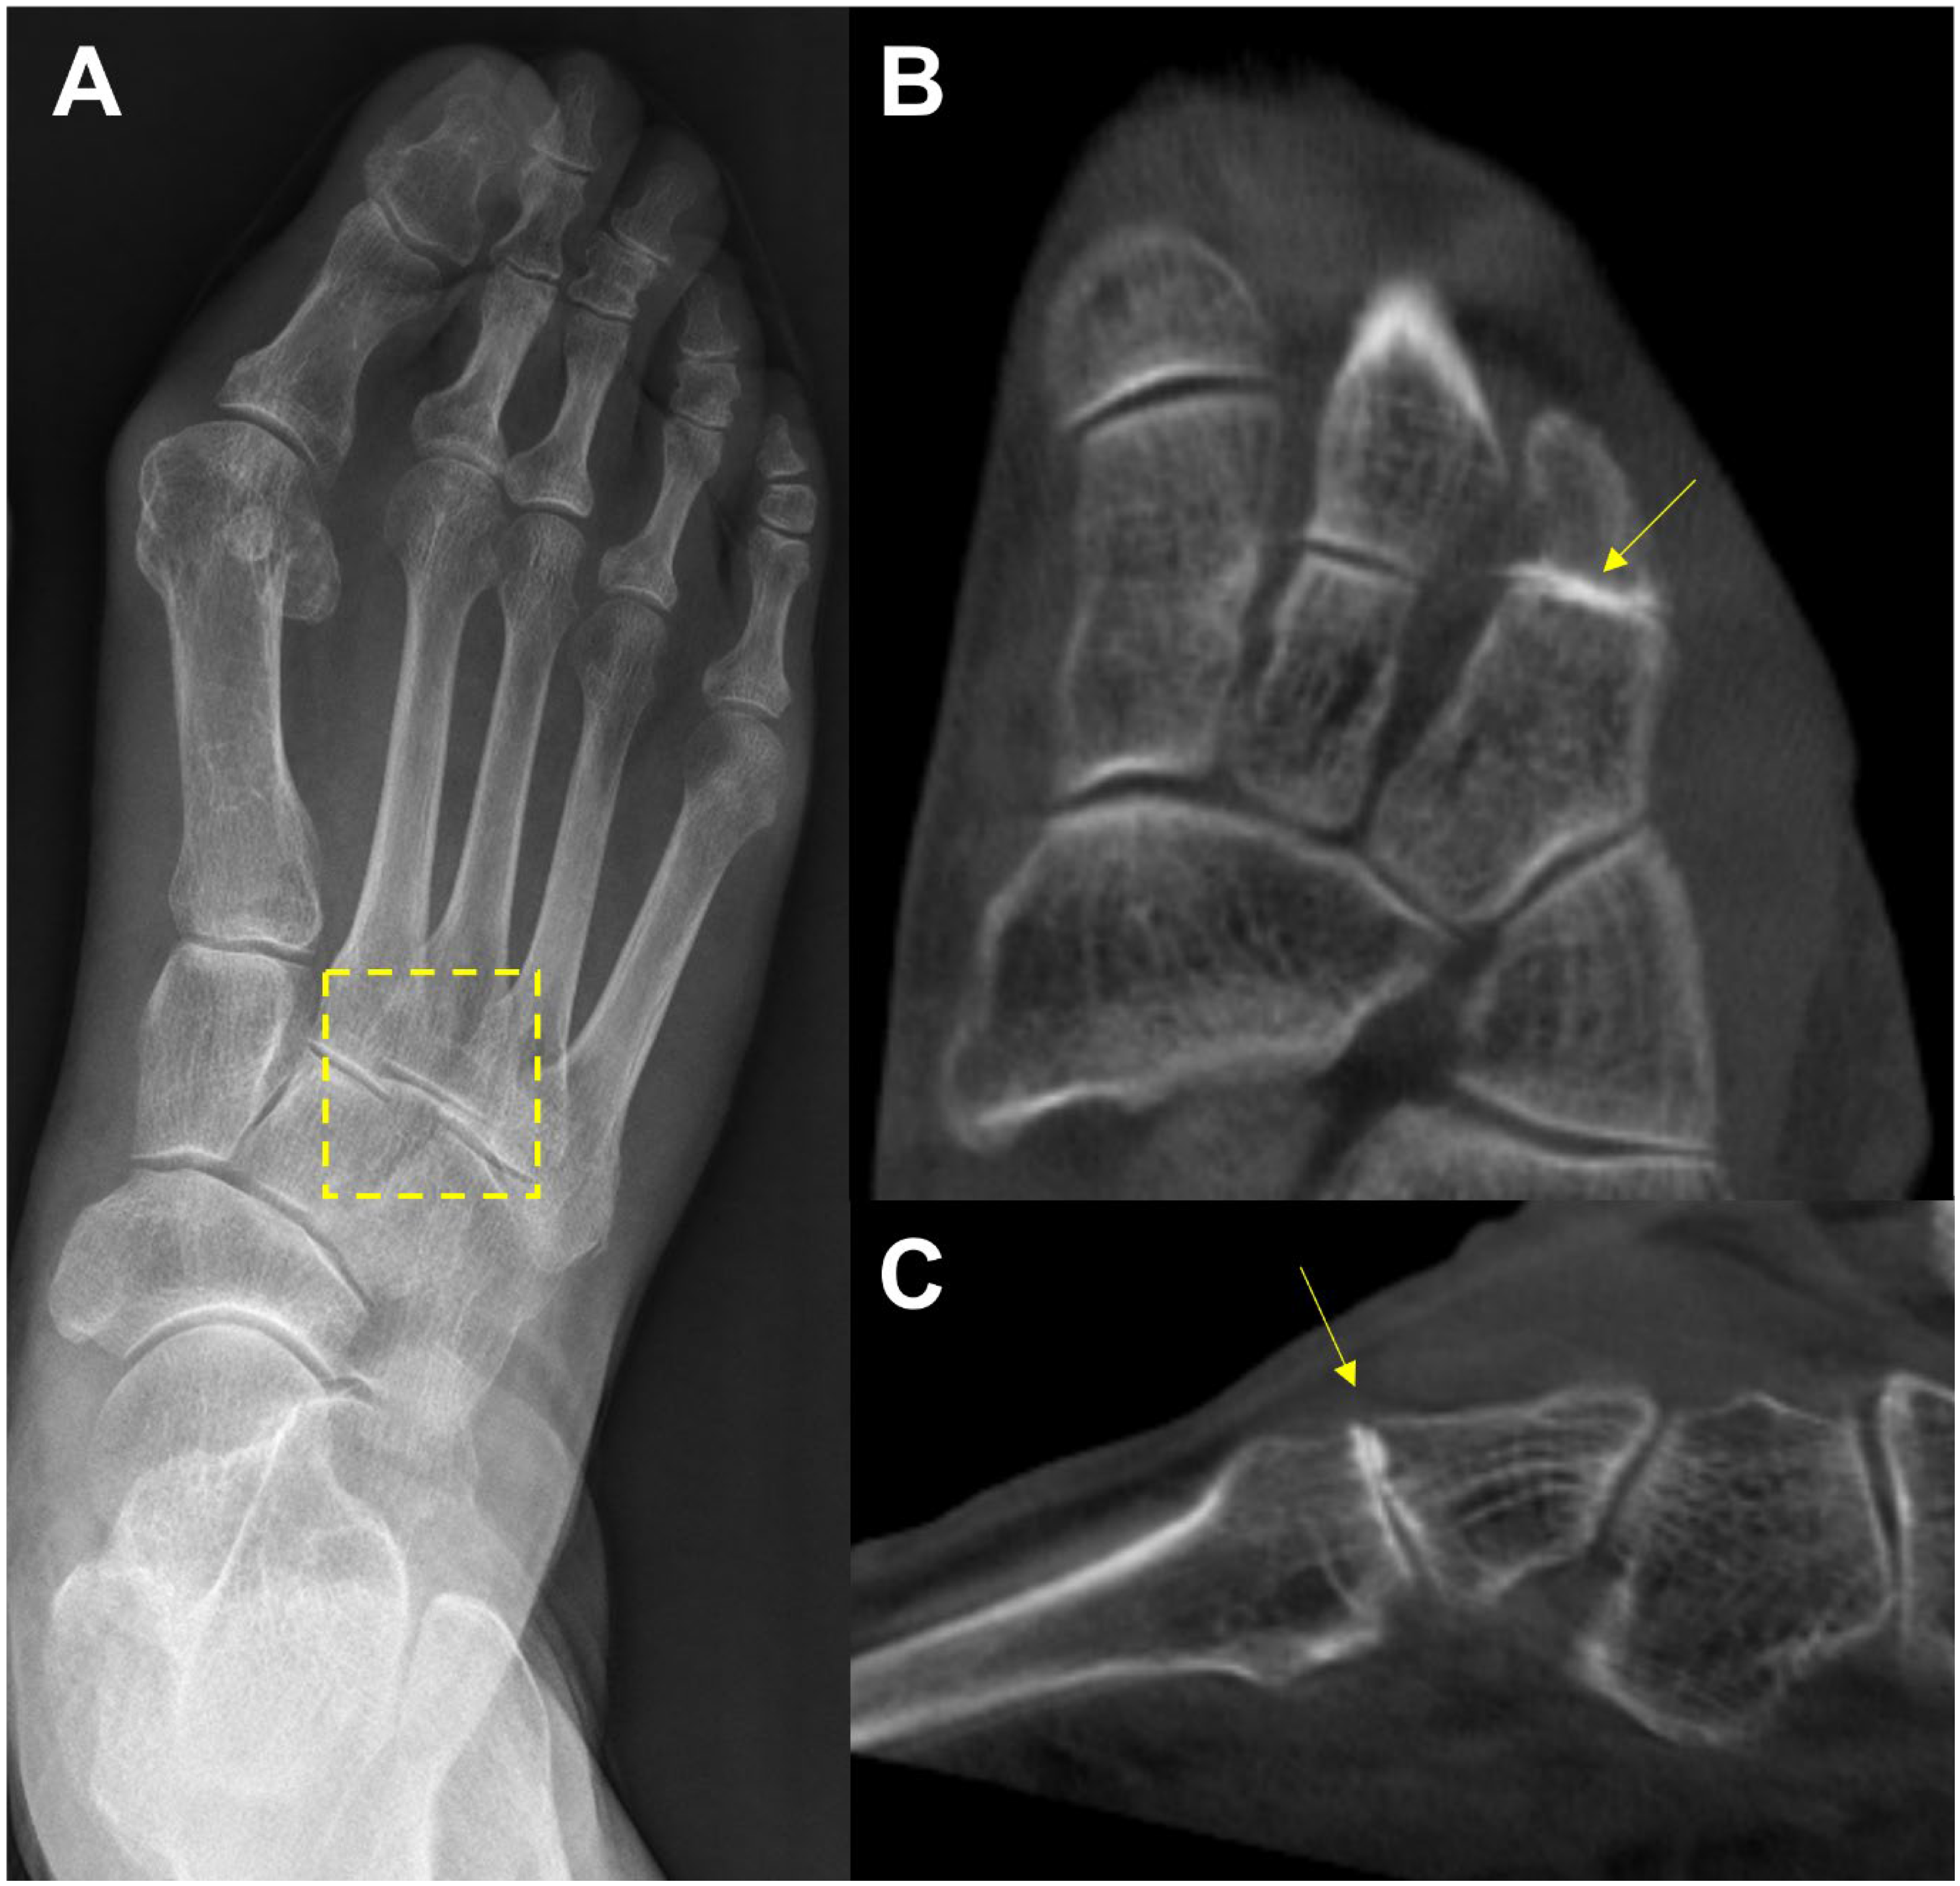

In the midfoot, precise identification of associated articulations and osseous borders in conventional weight-bearing radiographs may not be handy because they can be affected by overlapping adjacent bones when viewed two-dimensionally [31] (Figure 6). For this reason, WBCT is an alternative, as it enables clear joint space visualization and enhanced bony landmark identification under physiological weight-bearing conditions. Steadman et al. compared weight-bearing radiographs and WBCT with regard to diagnostic accuracy in midfoot osteoarthritis [32]. They found that weight-bearing radiography demonstrated 61.5 to 72.5% sensitivity and 87.9 to 96.1% specificity in identifying midfoot osteoarthritis. It also showed less accurate localization of degenerative changes and a greater tendency to underestimate disease severity compared to WBCT. These findings indicate that WBCT would be a better diagnostic option in midfoot osteoarthritis as it provides an earlier and more reliable diagnosis.

Figure 6.

In the plain radiograph, osteoarthritis of the third tarsometatarsal (TMT) joint is not clearly visible (A, See box area); however, weight-bearing computed tomography (WBCT) reveals distinctive joint space narrowing and sclerotic changes (B,C; See arrow).